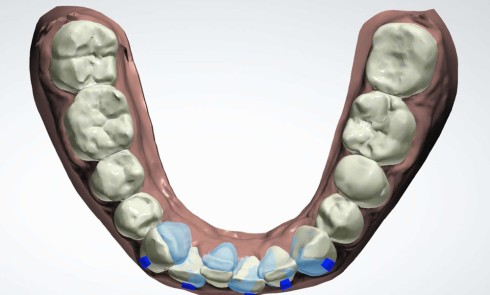

Présentation du cas clinique (fig. 1 à 3) Le patient, âgé de 58 ans, présente un encombrement dentaire mandibulaire de 5 mm dans...